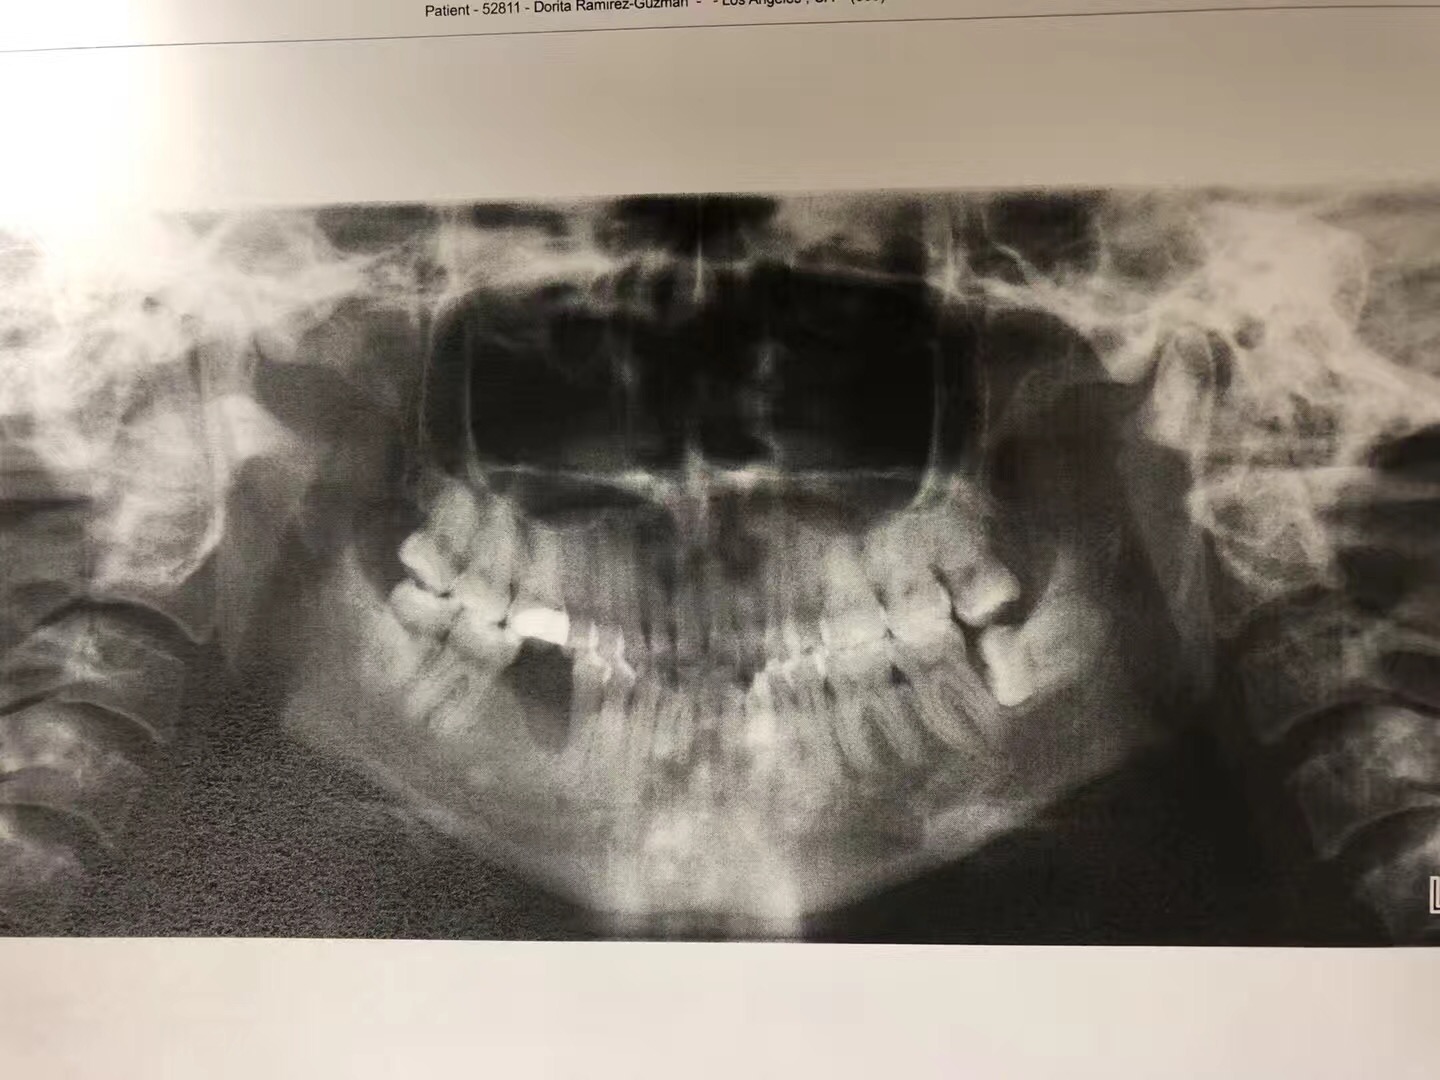

2016年,她感觉第一大臼齒的地方很疼痛去看了一般的牙醫,这位牙醫立即幫她拔了疼痛的牙齒,结果她的牙根却留在牙糟裏。后來,她来到我們南加大醫院的口腔外科,我的住院醫生见状,幫她把牙根拔了,結果引起骨壞死。这一年多来,住院醫生只有開消炎藥和漱口水給她,但一直未见好转,后来,住院醫生把这位患者病情告诉我,希望我能幫她。我了解病情后,若按照常规治疗,效果不明显。我采用了自己研發的新藥,第一次病人需要在诊所注射,之後,再把藥交給病人,譲病人携帶回家自己打。二個星期後,病人回診,骨頭已經好了,而且還長的和之前一样。她见到我激动的说,林医生是我的救命恩人。

今年,我研制治療骨壞死的藥將在美国口腔外科協會發表,这將是全世界第一個治疗癌症转移骨壞死的藥,经过多年的临床证明,完全可以治愈骨壞死,并且,將來可以广泛應用在骨科和足科方面的领域。

建议,癌症患者在静脉应用双膦酸盐前应对患者进行一次全面的口腔检查,拔掉不可修复的牙齿,清洁牙结石,完成所有侵袭性的牙科操作,达到最佳牙周卫生。使用后也要定期做口腔检查,保持良好口腔卫生,定期做牙周石的清洁,护理,减少蛀牙的产生。